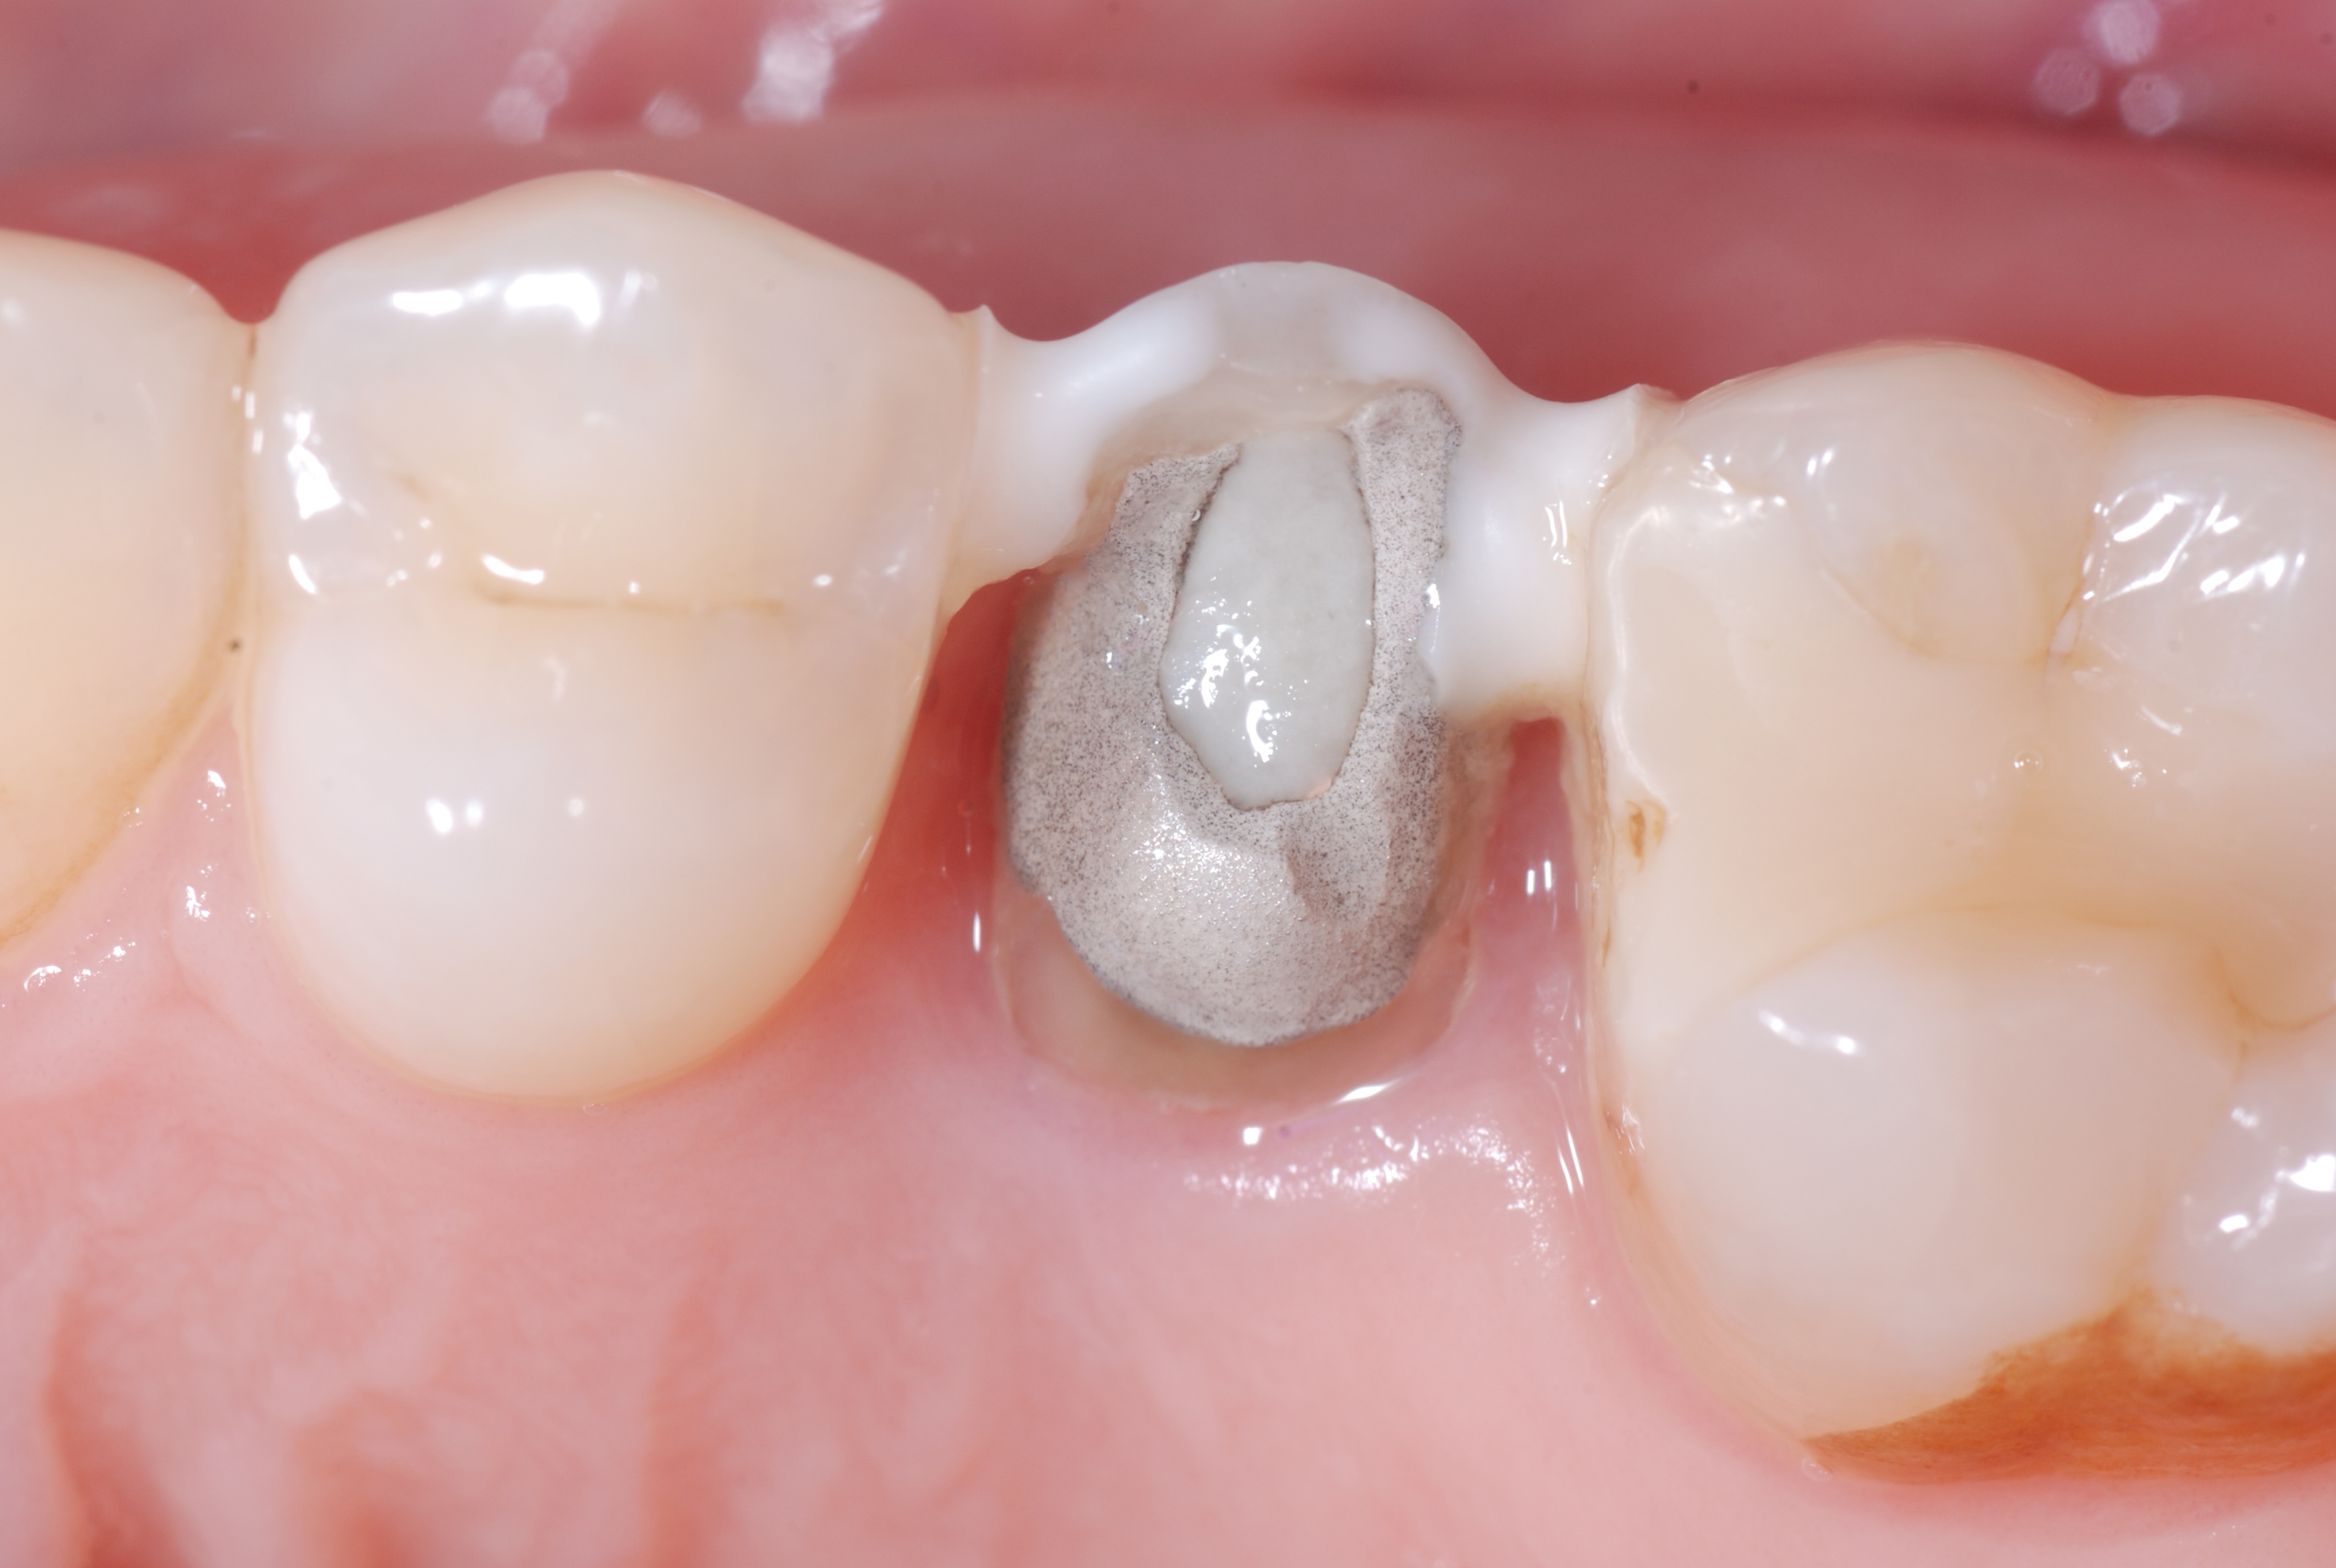

Figure 3

Figure 4

Figure 3. The same tooth immediately after the surgical extrusion.Figure 4. Tooth 25 five weeks after extrusion and endodontic retreatment (carried out by Dr. Francesco Piras). The two points of flowable composite used for splinting after extrusion and the temporary restoration in CVI are still present.